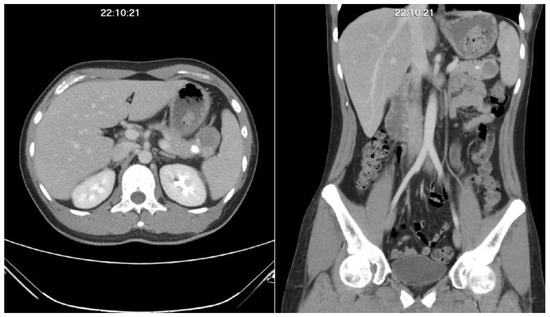

A Rare Case Report of Mesenchymal Chondrosarcoma with Pancreatic Metastasis

Background: Mesenchymal chondrosarcoma is a rare but aggressive subtype of sarcoma. The majority of involvement locates in the axial skeleton. Treatment modalities include radical surgery, local radiotherapy, and systemic chemotherapy. However, the long-term survival outcome remains poor. Case presentation: We present [...] Read more.

Background: Mesenchymal chondrosarcoma is a rare but aggressive subtype of sarcoma. The majority of involvement locates in the axial skeleton. Treatment modalities include radical surgery, local radiotherapy, and systemic chemotherapy. However, the long-term survival outcome remains poor. Case presentation: We present the case of a 33-year-old male with a palpable chest wall mass for one year, diagnosed with mesenchymal chondrosarcoma with surgical removal. Later, he had an unusual pancreatic tail tumor as the first presentation of disease metastasis which was proven by surgical resection one year later. Conclusion: Although mesenchymal chondrosarcoma locates mainly in the axial skeletal system, extra-skeletal soft tissue or organ involvement might be seen occasionally. Active surveillance with multidisciplinary team management could significantly prolong survival outcomes. Full article